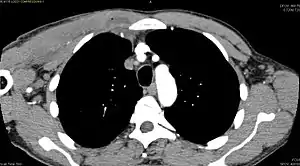

Diagnostic methodDiagnostic method used for PM includes ultrasound, CT scan and MRI. Ultrasound can be helpful in showing muscular heterogeneity or a purulent collection but it is not useful during the first stage of the disease. CT scan can confirm the diagnosis before abscesses occur with enlargement of the involved muscles and hypodensity when abscess is present, terogenous attenuation and fluid collection with rim enhancement can be found. MRI is useful to assess PM and determine its localization and extension